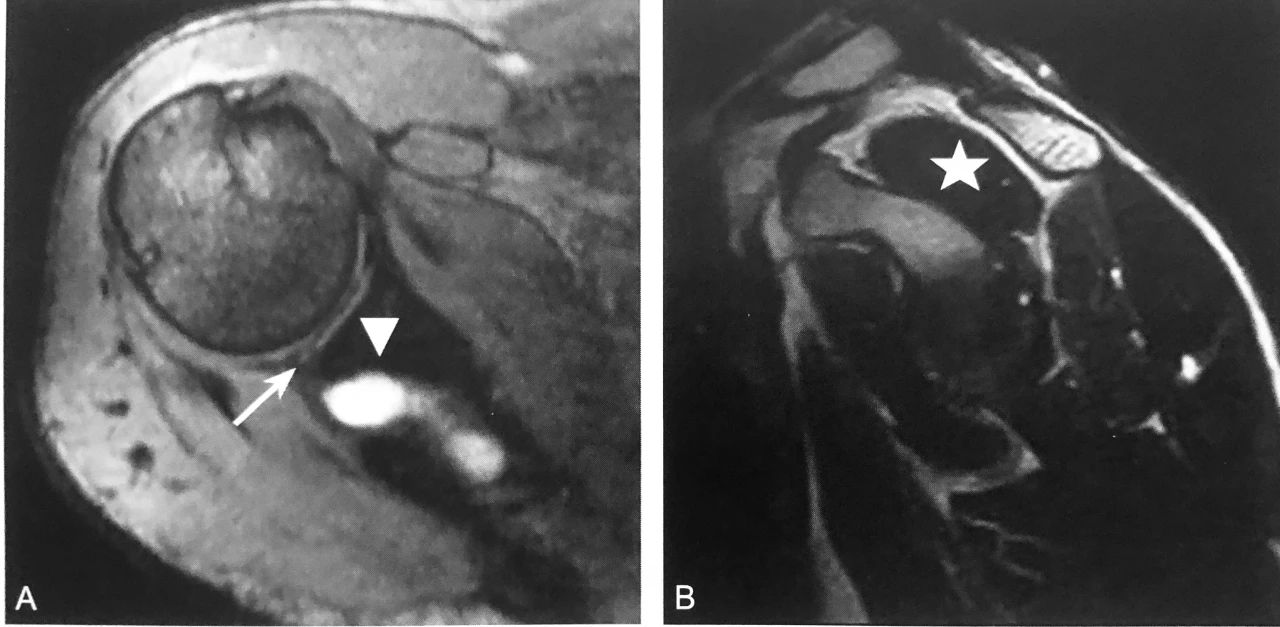

双肩锁关节征:A 图冠状位压脂 PD 序列显示,肩峰关节面下可见游离的条状、未融合肩缝小骨(箭头),肩锁关节囊积液,伴肩峰下-三角肌下滑囊积液,同时可见冈上肌肌腱撕裂(三角);B 图矢状位压脂 PD 序列显示:未融合肩峰小骨与肩峰关节面、肩锁关节形成双肩锁关节,肩锁关节囊积液,伴肩峰下-三角肌下滑囊积液(箭头)

判读要点:

1、在肩关节 MRI 冠状位或矢状位观察;

2、须同一层面同时观察到肩锁关节及肩峰小骨;

3、注意双肩峰关节征与第二肩锁关节区别;

4、观察肩峰小骨是否稳定,如不稳定,是否与邻近软组织产生撞击,此时应注意观察是否伴有周围积液、水肿、肩锁关节损伤及肩袖损伤。